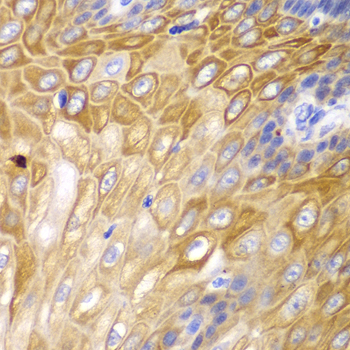

ApplicationWB, IHC; Recommended dilution: WB 1:500 - 1:1000, IHC 1:50 - 1:100